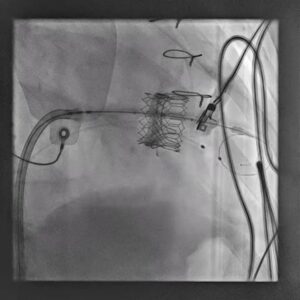

Figure 3. Expanded valve-in-valve prosthesis after deployment within the prior surgical mitral valve.

The patient underwent Transcatheter Mitral Valve-in-Valve Replacement using a 29 mm Edwards SAPIEN valve. Under advanced fluoroscopic and imaging guidance, the new valve was carefully positioned within the failing surgical mitral bioprosthesis and deployed in a controlled manner.

The objective was to create a well-seated valve-in-valve construct that would relieve the severe mitral obstruction, improve forward flow, and reduce transvalvular gradients. Controlled deployment is especially important in the mitral position, where anatomy, angle, and prior prosthetic material can influence the final result.

Following successful valve implantation, attention then shifted to the rhythm issue. During the same hospital admission, the patient underwent single-chamber permanent pacemaker implantation using a Medtronic–Vitatron system, thereby addressing the complete heart block and providing reliable ventricular pacing support.